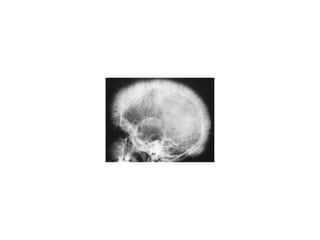

• A “crew cut” skull x-ray appearance may be seen

THALASSEMIAS • AWIDE VARIETY of diseases involving GLOBIN synthesis, COMPLEX genetics • Alpha or beta chains deficient synthesis involved • Often termed MAJOR or MINOR, depending on severity, silent carriers and “traits” are seen • HEMOLYSIS is uniformly a feature, a microcytic anemia • A “crew cut” skull x-ray appearance may be seen

• #29 Note the “spiculated” appearance of the outer table of the skull due to extreme erythroid hyperplasia!